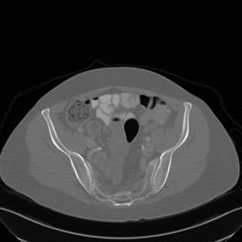

In this work, we present Eformer - Edge enhancement based transformer, a novel architecture that builds an encoder-decoder network using transformer blocks for medical image denoising. Non-overlapping window-based self-attention is used in the transformer block that reduces computational requirements. This work further incorporates learnable Sobel-Feldman operators to enhance edges in the image and propose an effective way to concatenate them in the intermediate layers of our architecture. The experimental analysis is conducted by comparing deterministic learning and residual learning for the task of medical image denoising. To defend the effectiveness of our approach, our model is evaluated on the AAPM-Mayo Clinic Low-Dose CT Grand Challenge Dataset and achieves state-of-the-art performance, $i.e.$, 43.487 PSNR, 0.0067 RMSE, and 0.9861 SSIM. We believe that our work will encourage more research in transformer-based architectures for medical image denoising using residual learning.